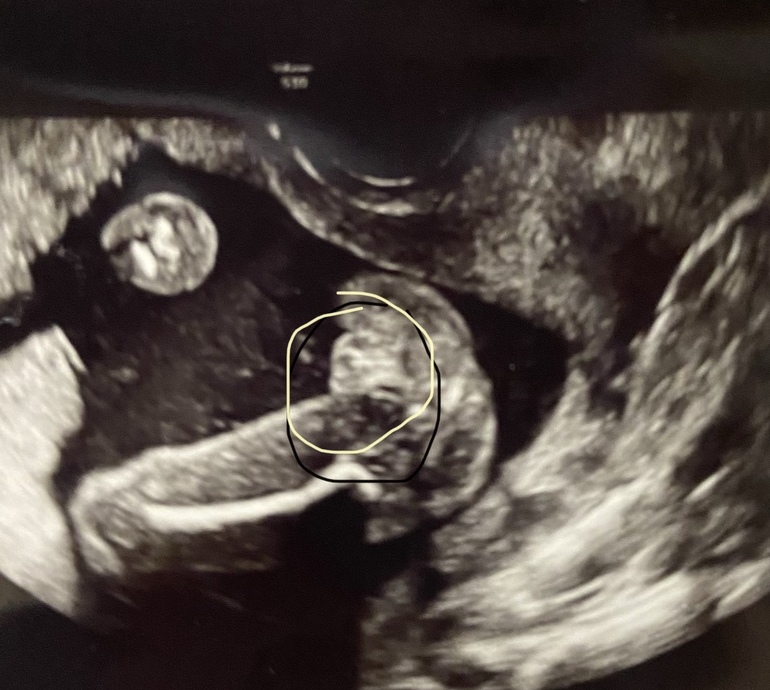

Пытаюсь понять, что меня ждет. Какими будут третьи роды. Да и вторая половина беременности тоже пугает... 5 лет назад была ИЦН. Теперь хожу, переживаю. На УЗИ была полторы недели назад - всё ок. Шейка хорошая.

4️⃣ ниже фото УЗИ - это же точно девочка?